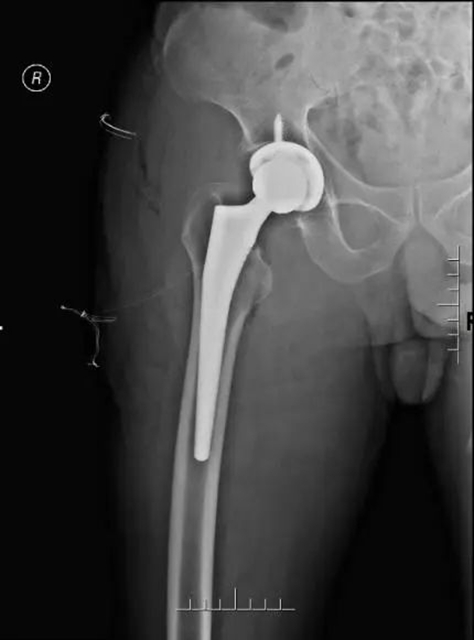

王爷爷术后X线

无独有偶,在五一节假日期间,李忠教授团队还为72岁股骨颈骨折患者王爷爷完成了全髋关节置换术,为两位年过八旬的股骨颈骨折老人行急诊人工全髋关节置换手术。手术患者平均年龄高达86岁,从患者受伤到接受手术的平均时间不到1天,所有手术均取得了成功。李忠教授团队多次冲破高龄禁区,让老人们重新站了起来。